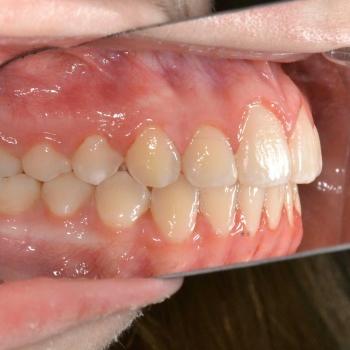

A kezelés megoldotta az összes fogszabályozással kapcsolatos problémát, így egy funkcionálisan és esztétikailag is megfelelő harapást kaptunk.

A kezelés teljes időtartama: 2 év